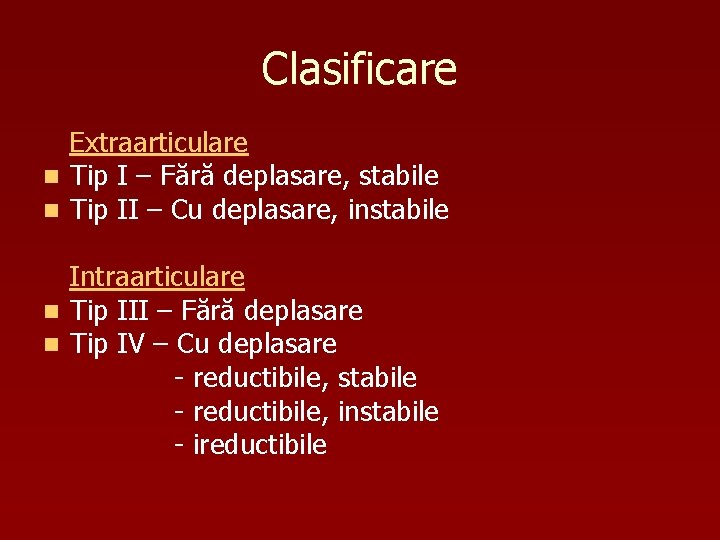

Clasificare Extraarticulare n Tip I – Fără deplasare, stabile n Tip II – Cu deplasare, instabile Intraarticulare n Tip III – Fără deplasare n Tip IV – Cu deplasare - reductibile, stabile - reductibile, instabile - ireductibile